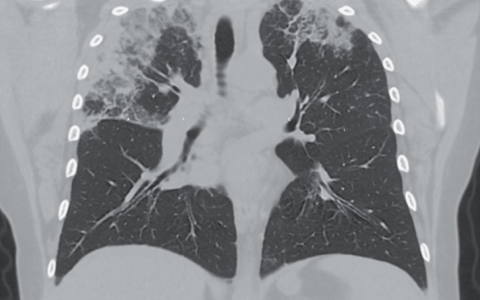

A 77-year-old man with metastatic lung adenocarcinoma presented to the emergency department with a 2-week history of dyspnea. Imaging studies showed a pleural effusion on the right side, previously known liver metastases and perihepatic fluid, and new intrahepatic dilatation of the biliary ducts. A chest tube was placed, and the color of the drained pleural fluid was olive brown. What additional pleural-fluid test is most likely to reveal the diagnosis?

正确答案是胸腔积液胆红素水平。胸腔积液检查显示总胆红素水平为8.2 mg / dl,直接胆红素水平为7.5 mg / dl。胸水甘油三酯水平正常,培养和细胞学检查结果为阴性。诊断为胆汁性胸腔。胆汁流入胸膜腔时发生胆汁性胸腔。在此例中,其机制被认为是肝转移引起的膈肌缺损。